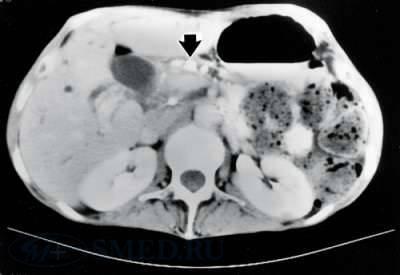

КТ является рентгенологическим методом высокой разрешающей способности, достаточно широко используемым при исследовании поджелудочной железы. В принципе, метод позволяет получить данные, аналогичные получаемым при ультразвуковом исследовании, однако в ряде случаев дает возможность уточнить последние, например, при ожирении больного, наличии метеоризма, преимущественной локализации изменений в области хвоста железы. Вместе с тем, встречаются случаи, когда очаговые изменения, выявленные при УЗИ, не обнаруживаются при КТ (изоденсны), или наоборот и, таким образом, оба исследования дополняют друг друга. Учитывая высокую стоимость КТ, ее применение следует считать необходимым в случаях, когда на основании УЗИ не удается создать достаточно четкое представление о патологических изменениях в поджелудочной железе (образование изоэхогенно частично).

В норме поджелудочная железа определяется на компьютерных томограммах в виде относительно гомогенного образования S-образной формы. Признаками поражения железы являются, неоднородность ее тени с участками уплотнения и разряжения, расширения, сужения и деформации протоков, одиночные или множественные полостные жидкостные образования. Для ложной кисты, как и при УЗИ, характерно наличие капсулы и однородное или неоднородное (при наличии в полости секвестров или замазкообразного детрита) содержимое. Высока разрешающая способность КТ при наличии в железе обызвествлений и протоковых конкрементов. Злокачественные новообразования выглядят при КТ очагами, плотность которых ниже плотности железы.

Рис. 3. КТ снимок. Стрелкой указаны кальцификаты в просвете протока поджелудочной железы.